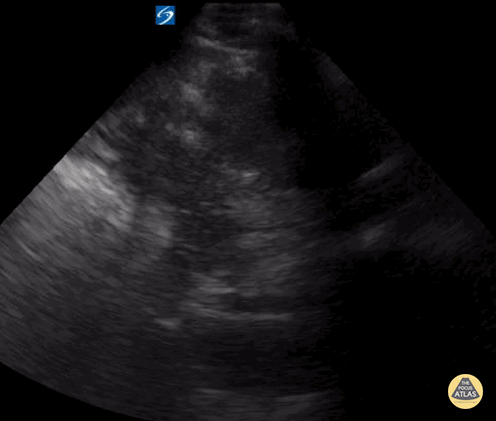

Normal LUQ FAST view Contributor: Kathryn Pade, MD

View: Unspecified Parasternal Long Axis Parasternal Short Axis Apical Four-Chamber Subcostal Four-Chamber Subcostal Inferior Vena Cava Right Upper Quadrant Left Upper Quadrant Suprapubic Longitudinal Suprapubic Transverse Subxiphoid Anterior Thoracic Phrenic